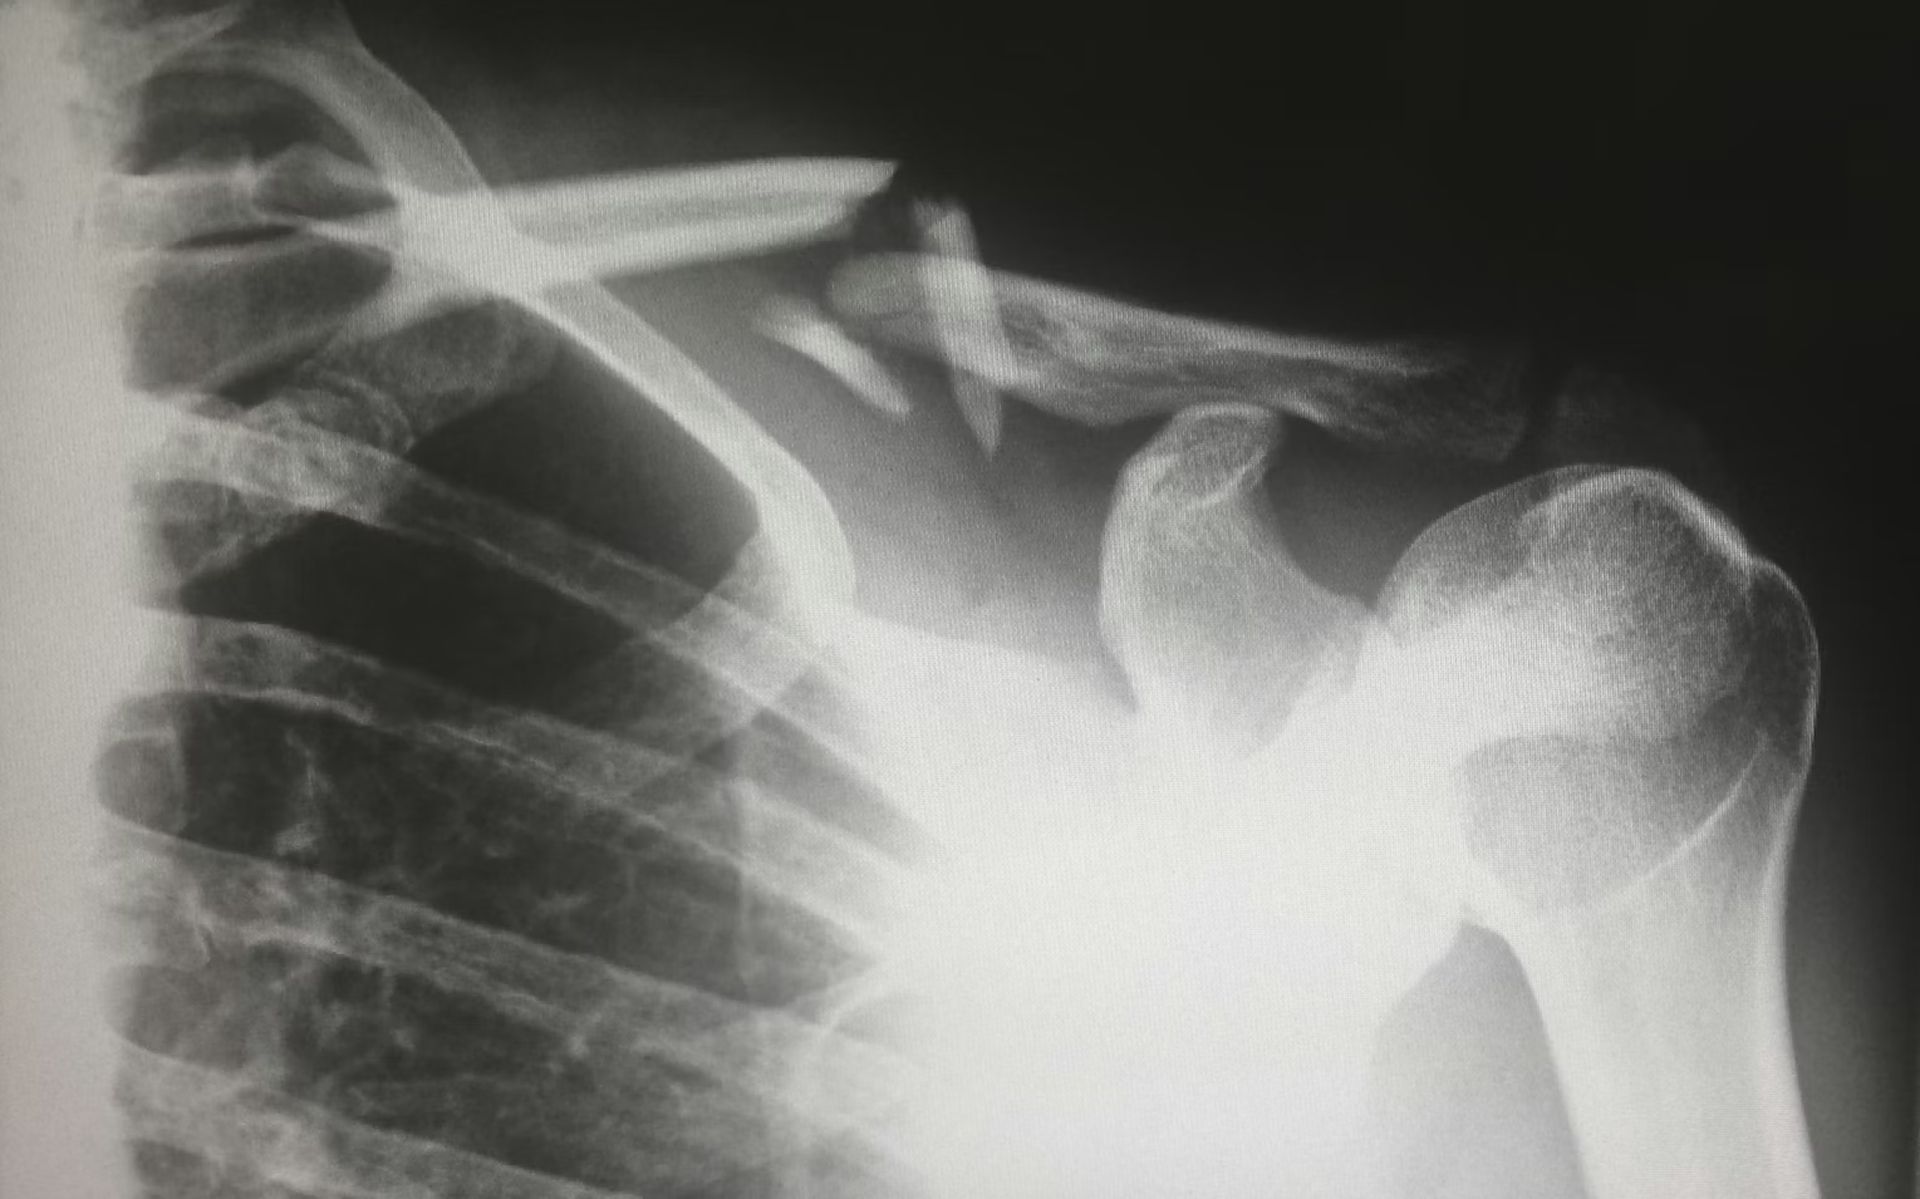

Οι ιατρικές σαρώσεις που δημιουργούνται από AI αποδεικνύονται σχεδόν αδιάκριτες από την πραγματικότητα

Οι ακτίνες Χ που παράγονται από τεχνητή νοημοσύνη μπορούν τώρα να φαίνονται αρκετά πειστικές ώστε να παραπλανήσουν ακόμη και ειδικούς ακτινολόγους, σύμφωνα με μια μελέτη που δημοσιεύθηκε στις 24 Μαρτίου στο Ραδιολογίατο περιοδικό της Radiological Society of North America. Η έρευνα διαπίστωσε ότι οι ακτινολόγοι ήταν σε θέση να προσδιορίσουν σωστά εάν οι εικόνες ακτίνων Χ ήταν πραγματικές ή συνθετικές μόνο στο 75% του χρόνου κατά μέσο όρο, παρά το γεγονός ότι γνώριζαν ότι οι ψεύτικες εικόνες περιλαμβάνονταν στο σύνολο δεδομένων.

Ο επικεφαλής συγγραφέας Mickael Tordjman, ακτινολόγος στην Ιατρική Σχολή Icahn στο Όρος Σινά στη Νέα Υόρκη, είπε ότι τα ευρήματα δείχνουν πόσο έχει προχωρήσει η συνθετική ιατρική απεικόνιση. «Η μελέτη μας δείχνει ότι αυτές οι πλαστές ακτινογραφίες είναι αρκετά ρεαλιστικές για να εξαπατήσουν τους ακτινολόγους, τους πιο άρτια εκπαιδευμένους ειδικούς ιατρικών εικόνων, ακόμη και όταν γνώριζαν ότι υπήρχαν εικόνες που δημιουργήθηκαν από AI», είπε.

Ο Tordjman σημείωσε ότι ορισμένες συνθετικές εικόνες εξακολουθούν να περιέχουν διακριτικά προειδοποιητικά σημάδια, συμπεριλαμβανομένων των οστών που φαίνονται υπερβολικά λεία, των αγκάθων που φαίνονται αφύσικα ίσιες και των σχεδίων αιμοφόρων αγγείων που φαίνονται πολύ ομοιόμορφα. Ωστόσο, η μελέτη δείχνει ότι η οπτική επιθεώρηση από μόνη της δεν αποτελεί πλέον αξιόπιστη ασφάλεια. Οι συγγραφείς ζήτησαν αντίμετρα όπως η αόρατη υδατοσήμανση και οι κρυπτογραφικές υπογραφές που εφαρμόζονται τη στιγμή της λήψης των εικόνων.